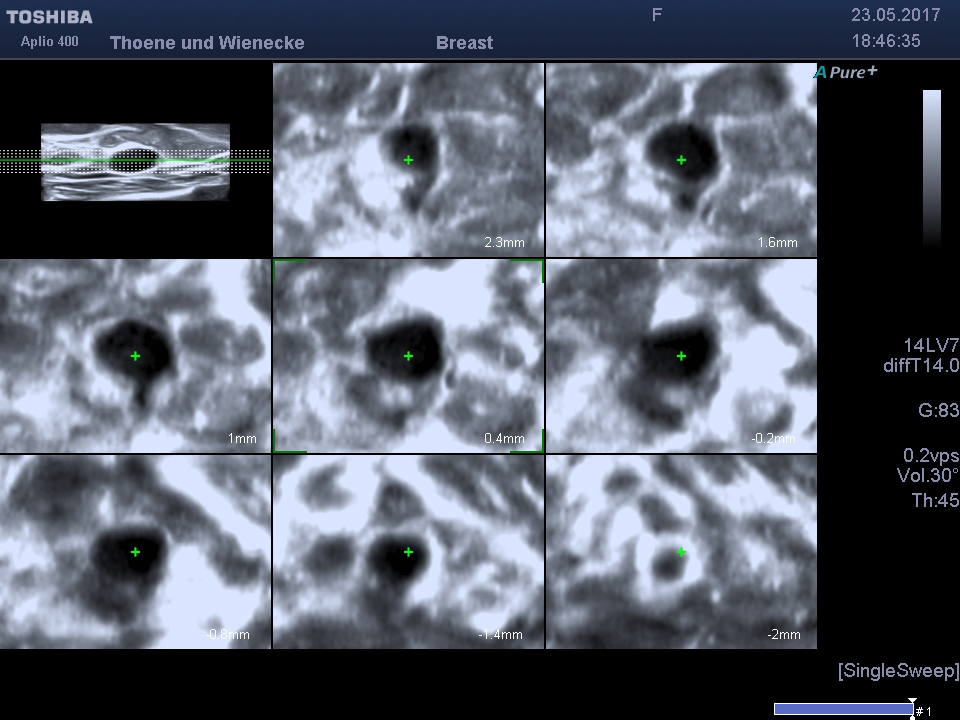

3D Sonographie der Brustdrüse

Was ist der Unterschied zur normalen Sonographie?

Der Ultraschall ist eine Untersuchung ohne Strahlenbelastung. In unsrer Praxis werden hochauflösende Ultraschallköpfe verwendet, die eine hohe Genauigkeit und sehr gute Auflösung ermöglichen. D.h. auch kleinste Veranderungen können schon gesehen werden. Mit der 3 D Sonographie können Veränderungen des Gewebes in ihrer Abgrenzung zum normalen umgebenden Gewebe besser beurteilt werden als nur mit der 2 D Methode. Bösartige Knoten bilden Ausläufer in das umgebende Gewebe, die wie kleine Strahlen einwachsen. Diese Phämomene können mit der 3 D Sonographie beurteilt werden, die Unterscheidung zwischen gutartigen und bösartigen Veränderungen wird genauer und die Rate an unnötigen Biopsien kann vermindert werden.